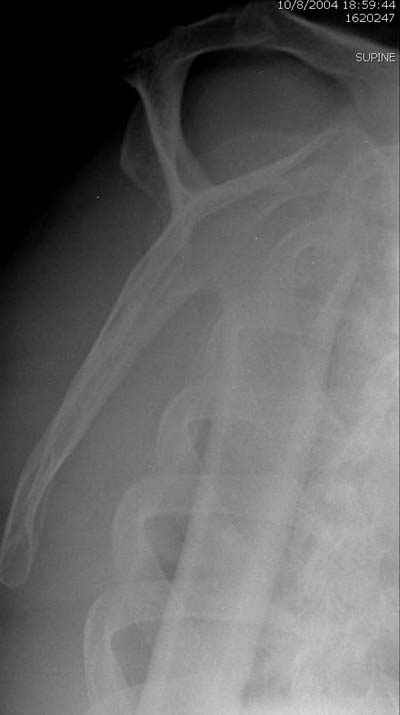

сделать закрытую репозицию с помощью ЭОПа совсем не сложно, после этого еще проще провести 3-6 спиц и получить красивую рентгенограмму. Есть только небольшая проблема это ROTATOR CUFF. Для плечевого сустава только костное восстановление не достаточно. для функции плечевого сустава нужны вращатели.

Давайте представим себе состояние манжетки вращателей после вывиха плеча, а еще и с отрывным переломом бугров. Головка может и прирастет, еесли не будет аваскулярного некроза, но хорошего функционального результата не ждите.

Висеть будет красиво. У людей физически активного периода жизни нужно открыть, восстановить костную анатомию и восстановить сухожильный аппарат.

В этом плане Locking plate очень хороша так как позволяет начать движения сразу после операции.

Клинические снимки - 3 недели после операции

с уважением М. Беренштейн